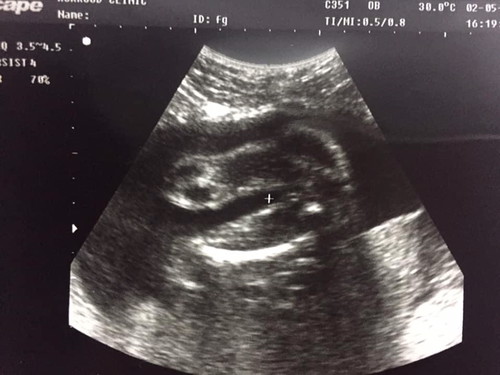

แบบนี้ ชายหรือหญิงคะ

แบบนี้ ชายหรือหญิงคะ แม่ๆ ????

ผู้หญิง เห็นกลีบ

ลูกสาวค่ะแม่